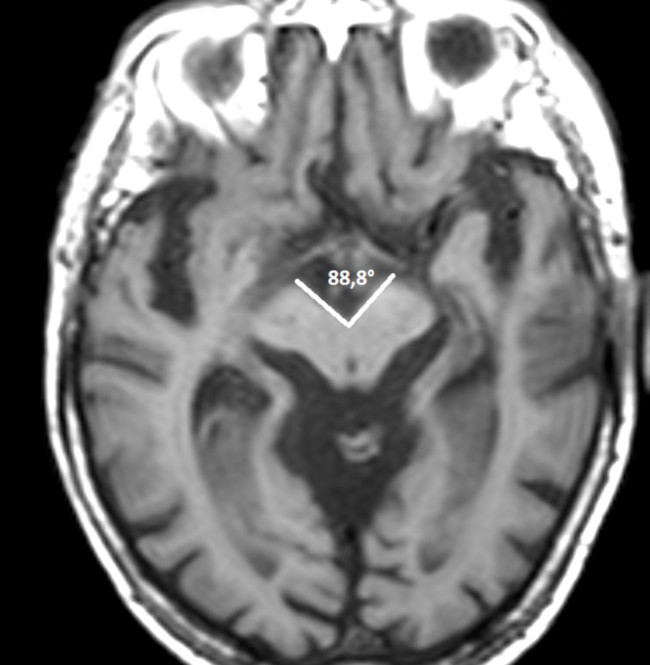

Es una medida utilizada para cuantificar la enfermedad neurodegenerativa conocida como síndrome de Steele-Richardson-Olszewski (SSRO). Esa patología se caracteriza por la atrofia selectiva del tronco encefálico, especialmente a nivel de los pedúnculos cerebrales, generando aumento de la apertura en la cisterna interpeduncular valorada en secuencias axiales de TC o RM.24

En un corte axial de una RM de cerebro, a la altura de los tubérculos mamilares, se trazan dos líneas paralelas a los bordes mediales de los pedúnculos cerebrales hasta que contacten en su vértice, midiendo el ángulo que forman (►Fig. 7).2

Un valor de ángulo de pedúnculo cerebral mayor o igual a 62° permite corroborar el diagnóstico de SSRO, diferenciándolo de otras patologías neurodegenerativas con un menor grado de apertura, como lo es el síndrome de Parkinson (53-54°) o la Atrofia multisistémica (55-56°).24